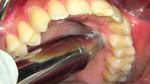

خراج الأسنان هو التهاب يصيب جذور الأسنان، بسبب البكتيريا التي تدخل إليه عبر التجاويف، ويكون على شكل انتفاخ بالقرب من الأسنان، ويرافقه ألم شديد، مع وجود قيح، وشعيرات دمويّة بارزة، وتعزى الإصابة به بشكل عام إلى إهمال نظافة الفم والأسنان، وإهمال علاجه يؤدي إلى تلف جذور الأسنان، وبالتّالي اختفاء الألم، ولكنّ ذلك لا يعني انتهاء المشكلة فالعدوى ستنتقل إلى أسنان أخرى، وتنخر في عظام الفك، ممّا يؤدي إلى تلفها وإذابتها وتجدد الألم.